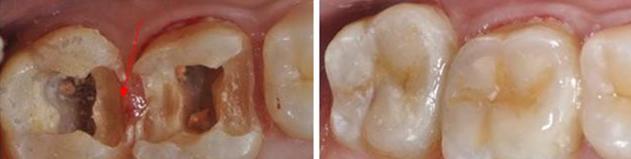

有啲蛀牙雖然外表睇上去只係一個小黑點,但其實內部已經齲壞嚴重,齲洞中嘅腐質含有大量被感染嘅牙體組織,補牙前需要去除齲洞中嘅腐質。如果唔將腐質去除乾淨就直接補牙,一方面充填材料好容易脫落,另一方面腐質中嘅細菌會繼續侵蝕健康嘅牙體組織,導致齲壞程度進一步加深。

補牙需要製備成一定形狀嘅窩洞來進行修復,醫生會在儘量唔破壞正常牙體組織嘅情況下,將腐質同埋剩餘較薄弱嘅牙體組織清除修整乾淨,從而獲得穩固嘅地基。